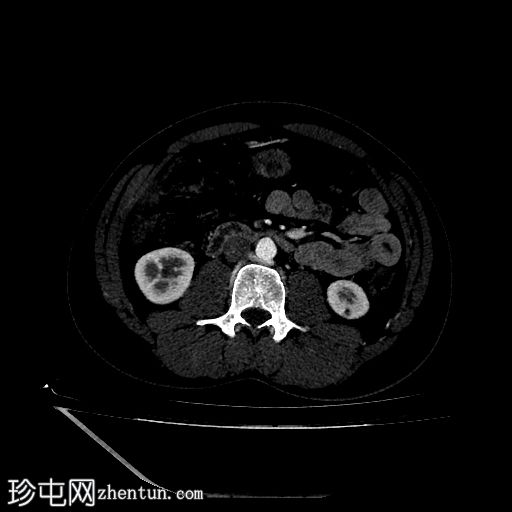

轴位

非增强

2.jpg

轴位增强扫描

动脉期

3.jpg

门静脉期

4.jpg

延迟期

5.jpg

CT肾血管造影显示一条起源于左肾下段的副肾静脉,该静脉环绕主动脉走行,并接受来自腰静脉的属支,走行于主动脉后方,最终汇入下腔静脉。

双侧肾脏集合系统重复,分为上极和下极两部分。右侧输尿管在中段汇合,而左侧输尿管在进入膀胱前仍部分分离,符合双侧部分输尿管重复畸形(双分输尿管)。

左肾下极可见一大小约7毫米的皮质性囊肿。